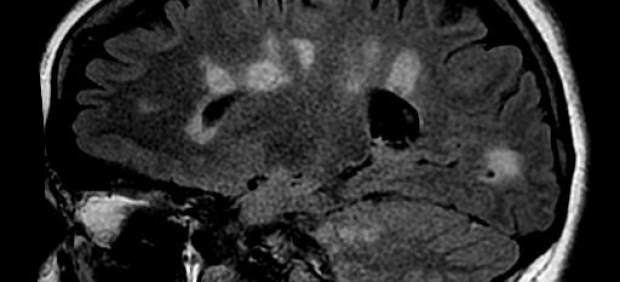

En la esclerosis múltiple se verifica un daño y una pérdida de mielina en varias áreas -de ahí el nombre de múltiple- del sistema nervioso central. Numerosas evidencias sean clínicas o experimentales indican que existe un proceso de desmielinización que determina daños o pérdida de la mielina y la formación de lesiones (placas).

Estas pueden cambiar de una fase inflamatoria inicial a una crónica, en la cual provoca características similares a las cicatrices, de ahí la denominación ‘esclerosis’, que significa «endurecimiento patológico de un órgano o tejido».